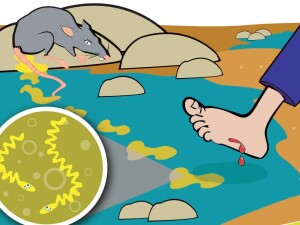

Лістеріоз — інфекційне захворювання, спричинене бактеріями, котрі широко розповсюджені у природі, у ґрунті, піску та воді.

Джерелом лістерій є дикі гризуни, тварини, а також дикі птахи, зокрема, голуби. Зараження людини може відбуватися при контакті з інфікованими тваринами, при вживанні рибної або тваринної продукції без термічної обробки (сире молоко, сирокопчені ковбаси, сир, особливо, придбаний на стихійних ринках), через забруднені овочі та фрукти.